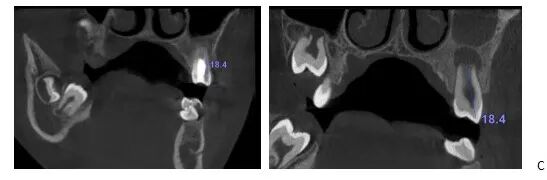

辅助检查:CBCT显示25牙根尖呈喇叭口样敞开,未发育完全,根尖低密度暗影。

CBCT矢状面显示25牙根尖未发育完成,根尖阴影

CBCT冠状面显示25牙根尖未发育完成,根尖阴影